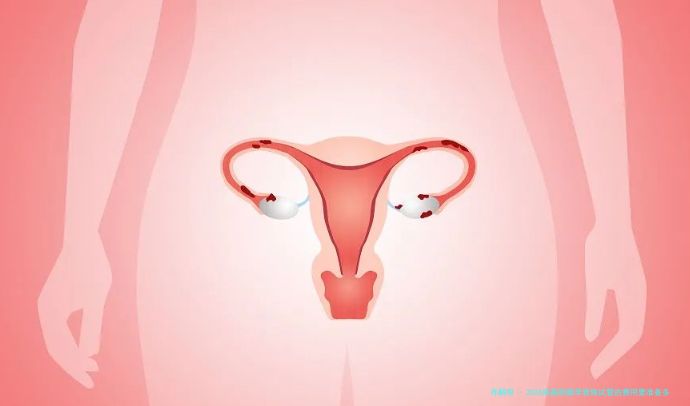

卵巢早衰是很多女性友人都会面临的难题,它并非仅影响着生育计划,也是对的自我健康致使必须的威逼。对于想要通过试管婴儿完成拥有孩子的心愿,认识相关费用以及抉择合适的医疗机构至关重要。2026年,南昌作为江西省的中心城市,医疗水平连续提高,为卵巢过早衰老病患提供了还要多选择。

卵巢早衰试管婴儿的费用是一个相比复杂的概念,因为它没有一个牢固值,受许多种要素影响,比如患者年纪、体质状况、卵子质量、胚胎移植次数等。一般来说,南昌卵巢过早衰老做试管婴儿的总价格在十五万元左右。

南昌卵巢过早衰老试管婴儿的成功率在60%左右,当然,具体成功率会根据患者的身体状况、年纪以及其他因素有所差距。想要提高试管婴儿成功率,建议您选择规范医疗机构,并积极配合医生的治疗方案,做好身体调理工作。